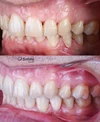

Diş Çapraşıklığı

Zirkonyum uygulamalar

Porselen uygulamaları

Laminate veneer